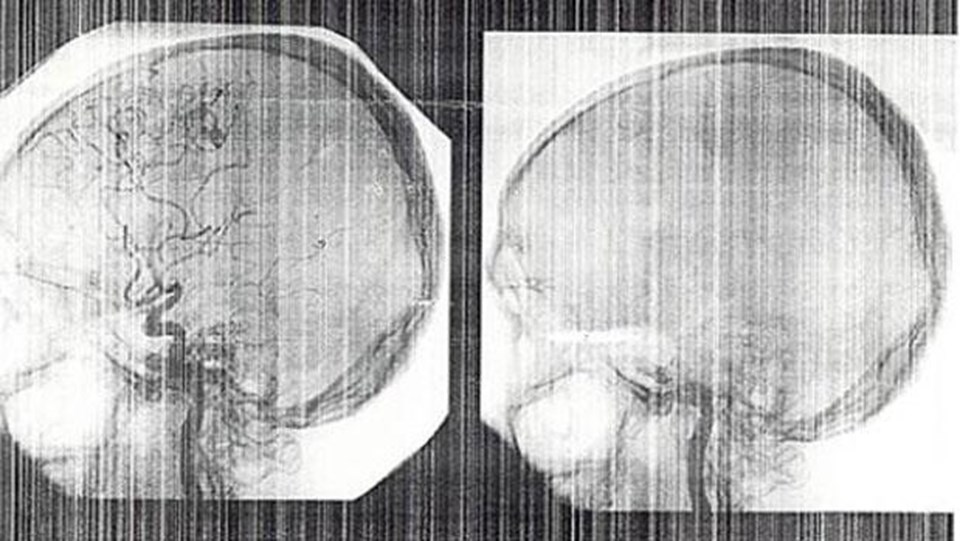

"Beyin ölümü, beyin, beyincik ve tüm yaşamsal merkezlerin bulunduğu beyin sapının fonksiyonlarının geri dönüşümsüz olarak yok olması durumudur. Beyin ölümü koma veya bitkisel hayat tabirleriyle aynı şey demek değildir. Beyin ölümü, tıbbi ölüm halini ifade eder. Beyin ölümünün geliştiği durumda kalp, böbrekler, akciğer ve karaciğer, solunum ve yaşam desteği sağlanması halinde kısıtlı bir süre daha çalışmaya devam eder. Ancak bu destekler durdurulursa kısa bir süre içinde tüm bu organ fonksiyonları da kaybedilir. Beyin ölümünün tanınması ve tanımlanması kritik bir süreçtir. Beyin ölümünün doğru, eksiksiz ve zamanında tanımlanması büyük önem taşımaktadır."

"Beyin ölümü kesin tanısı için, beyin hasarına yol açan hastalık veya süreçlerin ulaşılabilecek bir tedavisi olmamalı veya tüm tedavi girişimlerine yanıtsızlık bulunmalıdır. Hasta anestezik ilaçların, bilinç düzeyini etkileyebilecek ajanların, elektrolit dengesizliklerinin ve metabolik bozuklukların etkisinde olmamalıdır. Bunların yanında diğer tıbbi gereklilikler sağlandıktan sonra beyin ölümünün temel bulgularının değerlendirilmesine geçilir. Beyin ölümü klinik tanısının üç temel bulgusu derin koma durumu, beyin sapı reflekslerinin kaybolması ve solunum yokluğu testidir."